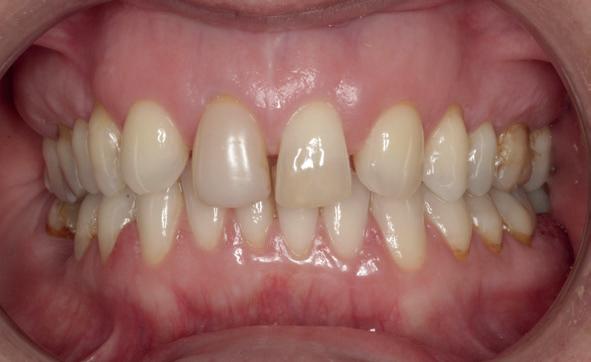

Casus

De patiënt, een 70-jarige man, had in het verleden tandheelkundige zorg ontvangen die zich kenmerkte door een ad hoc benadering. Er was geen sprake van een overkoepelend behandelplan of lange termijnvisie. De patiënt had naar eigen zeggen jarenlang niets

1. Studiofoto intake

aan zijn gebit gedaan behalve pappen en nathouden. Tandheelkundige zorg werd enkel verleend wanneer er zich een probleem voordeed (afbeelding 1, 3, 5).

De patiënt werd in de eerste fase gezien door de parodontoloog, implantoloog en restauratief behandelaar. Klinisch werden drie complicerende factoren vastgesteld: inadequate mondhygiëne, een ongunstige occlusale relatie en restauraties met gebrekkige marginale adaptatie met overhang. De patiënt werd opgenomen in het parodontale behandelprotocol.

De diagnose luidde lokaal parodontitis met ernstige furcatie aandoeningen; Stadium IV (vergevorderd); graad C (snel progressief) (afbeelding 7) De elementen die niet te behouden waren, werden geëxtraheerd.

Na afronding van de eerste twee behandelstappen werd parodontale stabiliteit bereikt, zoals waarneembaar op de parodontiumstatus en (röntgen)foto’s (afbeelding 6, 8). De patiënt toonde aantoonbare verbetering in mondhygiëne (afbeelding 4) en bleef gemotiveerd om de behandeling voort te zetten.